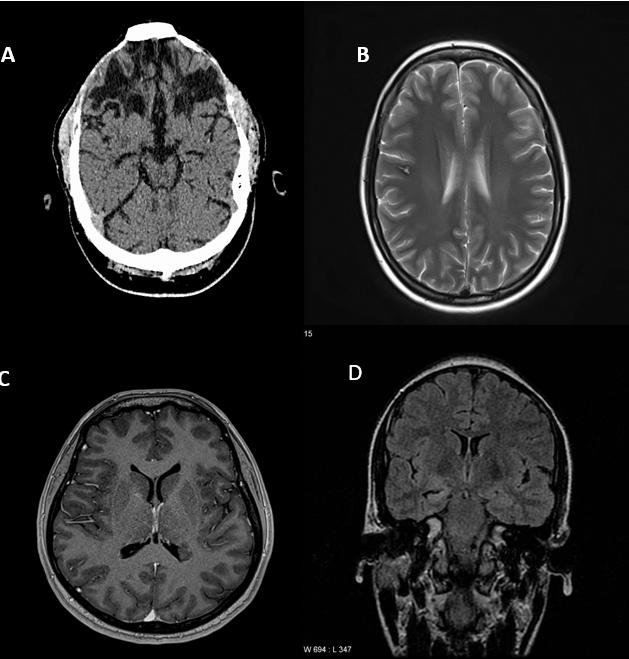

Figure 2: Neuroimaging showing epileptogenic lesions

(A) CT brain axial view (noncontrast) showing bifrontal encephalomalacia secondary to head injury; (B) MRI brain T2 axial showing cavernoma in R frontal lobe; (C) MRI T1 axial, post contrast sequence showing subependymal grey matter heterotopia at the left ventricular atrium; (D) MRI brain FLAIR Coronal sequence showing hippocampal sclerosis (right)

preceded by CT in certain clinical circumstances, such as acutely altered mental state or focal neurological deficit and is easily available compared to MRI in urgent scenarios. The preferred neuroradiological investigation for new onset seizures is 3 Tesla MRI brain with specific epilepsy protocol however many institutions have 1.5 T MRI imaging which would be sufficient in the initial work up. The images should be reviewed by a neuroradiologist provided with detailed clinical information including the suspected clinical epileptic focus. Figure 2 below shows some of the known epileptogenic lesions that can detected on neuroimaging. EEG remains an essential part of the work up of a patient with new seizures. It can offer a confirmation of suspected diagnosis in some cases, as well as vital information regarding epileptogenic focus and underlying epilepsy type. EEG after a new onset seizure can show epileptiform activity in approximately 29% of patients, however the cumulative rates of detecting epileptiform increases with repeated EEG. The usage of sleep deprived EEG also increases the rates of detecting clinically relevant abnormalities. EEG has greater utility in the evaluation of generalised seizures